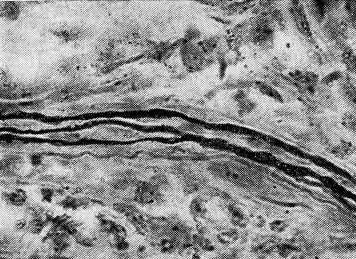

Рис. 1. Слизистая оболочка барабанной полости кролика № 2 после введения борного спирта в среднее ухо на протяжении месяца. Безмиелиновые нервные волокна с четкообразными вздутиями, в которых отмечается распад.×1350

При импрегнации по Грос—Бильшовскому в модификации Кампоса в описываемых элементах среднего уха обнаружены реактивные и некробиотические процессы. Отмечена гипераргентофильность многих нервных волокон, натеки и неравномерное расположение нейроплазмы. Безмиелиновые концевые фибриллы с рецепторными элементами также проявляли повышенное сродство к серебру при наличии варикозностей и вакуолизации последних. Имелись участки, где, наоборот, терминальные нервные волокна слабо воспринимали серебро и распадались на фрагменты.